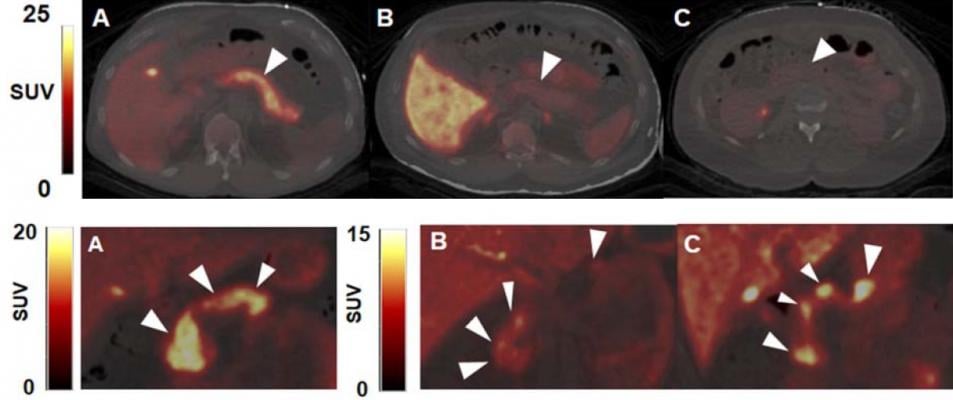

Beta cells and neurological tissues have common cellular receptors and transporters, so the Yale researchers screened brain radioligands for their ability to identify beta cells. Then, 12 healthy control subjects and two subjects with type 1 diabetes mellitus underwent dynamic PET/CT scans with six tracers.

The dopamine type 2/type 3 (D2/D3)-receptor agonist radioligand carbon-11 (11C)-(+)-4-propyl-9-hydroxynaphthoxazine (PHNO) was the only radioligand to demonstrate sustained uptake in the pancreas with high contrast versus abdominal organs such as the kidneys, liver, and spleen.

The results provide preliminary evidence that 11C-(+)-PHNO is a potential marker of beta-cell mass with 2:1 binding of D3 receptors over D2 receptors. While further research is needed before clinical application, 11C-(+)-PHNO is a promising way to differentiate the beta-cell mass of healthy individuals from those with type 1 diabetes mellitus, as well as track and guide therapies for diabetes patients.